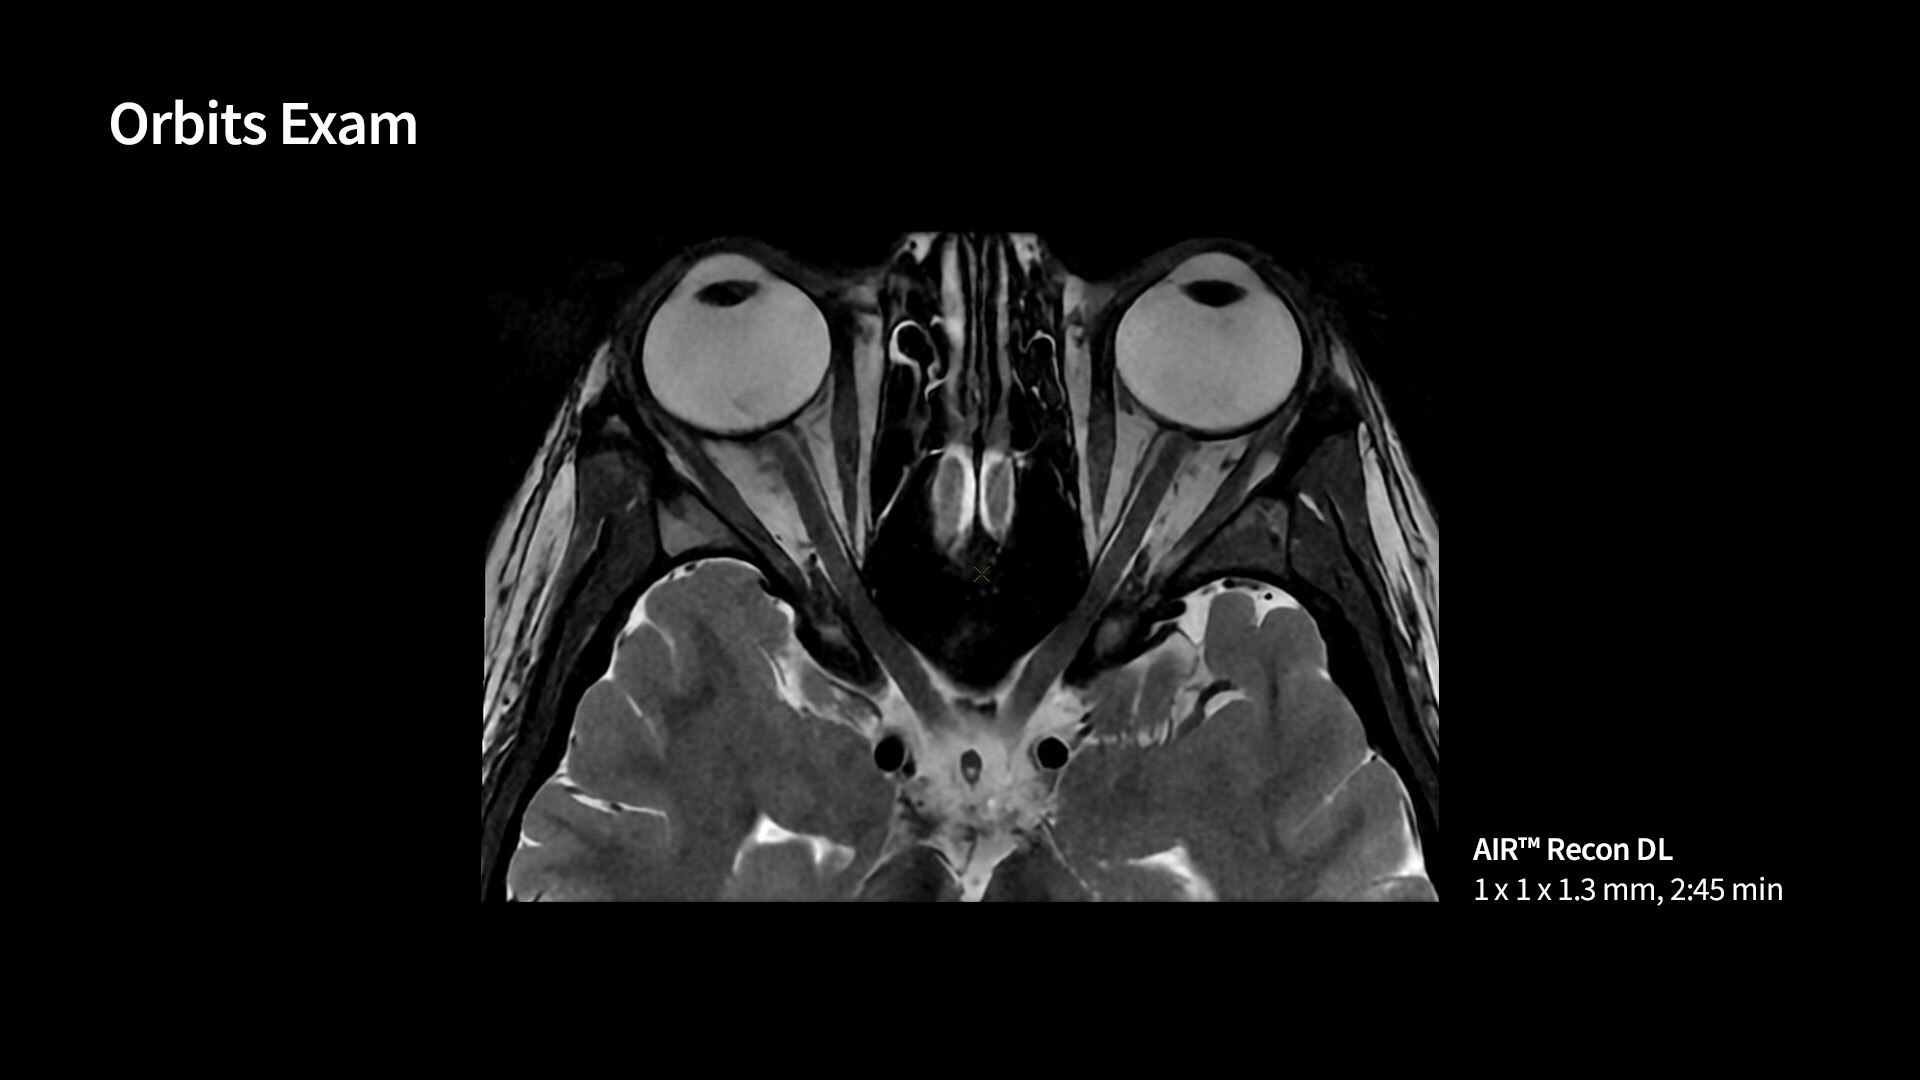

AIR™ Recon DL has revolutionized MR imaging with deep-learning based image reconstruction increased image quality, reduced scan time and improved SNR.